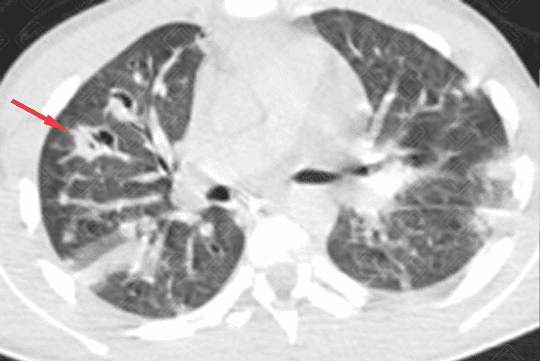

Descrição da lesão: Tomografia computadorizada do tórax (imagem axial e reformatação coronal) demonstrando opacidades nodulares bilaterais, esparsas e predominantemente periféricas, em vários estágios de escavação (setas vermelhas).

Embolia séptica: A embolia séptica pulmonar ocorre quando os fragmentos de trombo contêm microorganismos, em geral bactérias. Os principais fatores de risco incluem: uso de drogas intravenosas, presença de cateter intravascular, infecção generalizada, principalmente nos imunodeficientes, doença cardíaca congênita, tromboflebite séptica e processos supurativos da cabeça e pescoço. O agente mais comumente isolado em hemoculturas é o Staphylococcus aureus . Diante da suspeita clínica, podem ser solicitados radiografia ou tomografia computadorizada do tórax.

• Tomografia computadorizada do tórax: Nódulos em diferentes estágios de escavação, sendo mais numerosos na periferia dos pulmões e nos lobos inferiores. Podem ser observadas ainda consolidações geralmente subpleurais e cuneiformes.